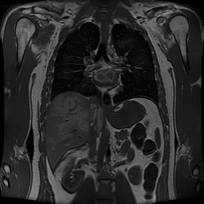

Compliance Consultants worked on both for regulatory and engineering projects on ionizing (x-ray tube technology) and non- ionizing (fluroscopy) imaging systems. Involved in early Computerized Axial Tomography systems as well as early soft issue (low-dose) digital imaging/enhancement systems using array processors.

We were at the forefront when digital radiography was first conceived adapting array processors to render digital images from vascular angiography. We matured into other imaging modalities...fluoroscopy, ultrasound, CAT scanners, MRI, PET, ....these mature products have derivative that include vessel analysis and calcium scoring softwar...Regulation Number: 21 CFR 892.2050, Product Code: LLZ

Compliance Consultants worked on both for regulatory and engineering projects on ionizing (x-ray tube technology) and non- ionizing (fluroscopy) imaging systems. Involved in early Computerized Axial Tomography systems as well as early soft issue (low-dose) digital imaging/enhancement systems using array processors.

We were at the forefront when digital radiography was first conceived adapting array processors to render digital images from vascular angiography. We matured into other imaging modalities...fluoroscopy, ultrasound, CAT scanners, MRI, PET, ....these mature products have derivative that include vessel analysis and calcium scoring softwar...Regulation Number: 21 CFR 892.2050, Product Code: LLZ